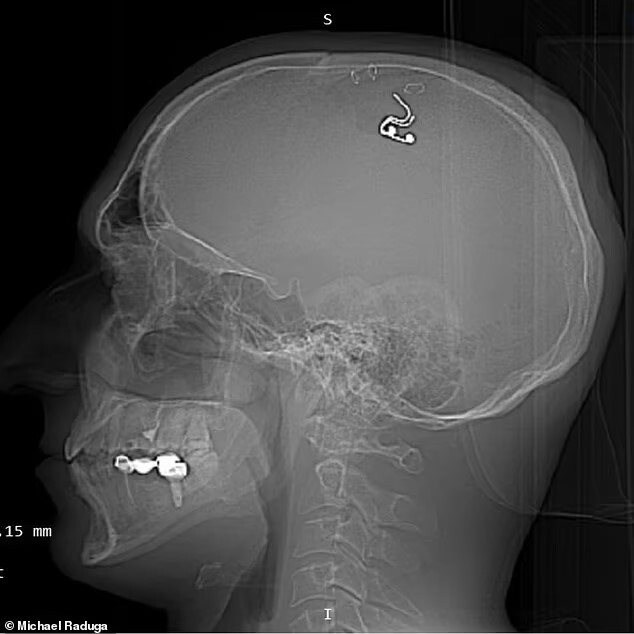

Просверлил себе голову дрелью и вживил в мозг чип: русский экспериментатор-исследователь хочет контролировать свои сны

22 ИЮЛЯ 2023г. 40-летний российский исследователь Михаил Радуга самостоятельно вживил себе в мозг имплант, чтобы "контролировать свои сны". Россиянин сделал себе операцию на головном мозге в своей гостиной в Казахстане

История экстремальной операции стала известна, благодаря "Твиттеру" стихийного экспериментатора и статье в британской "Дейли мейл". По мнению хирурга и пациента в одном лице, в ближайшем будущем люди смогут контролировать свои сновидения и направлять их в желаемую сторону.

Вживление чипа в мозг Радуга провел самостоятельно в собственной квартире в Алма-Ате, куда недавно переехал из России. Не имеющий квалификации нейрохирурга, новоиспеченный "биоробот" сравнил свой чрезвычайно опасный эксперимент с голливудским фильмом "Начало", утверждая, что однажды его "электрод" сможет изменить ход осознанных сновидений.

К хирургическому вмешательству Михаил Радуга готовился по роликам в "Ютьюбе", отрабатывая навыки на овцах. В конце концов день "икс" настал, и операция была проведена - в домашних условиях с использованием обычной дрели и других подручных инструментов. При этом, по его словам, он потерял более "литра крови", пытаясь пробить заднюю часть черепа строительным инструментом и фиксируя кожу скрепками. При этом никто из близких о его планах не догадывался.

"Впервые в истории мы провели прямую электрическую стимуляцию моторной коры головного мозга во время REM-сна, люцидных сновидений и сонного паралича, - ликует он. - Полученные результаты открывают фантастические перспективы для будущих технологий управления сновидениями".

Вживив себе имплант из платины и кремния, Радуга утверждает, что "поднялся на ступеньку выше", и теперь использует "силу электричества" для того, чтобы вызывать контролируемые сновидения.

"Дейли мейл" уточняет, что спустя пять недель после операции врачи извлекли инородное тело из его черепа.

Нейрохирург-консультант из Оксфордского университета Алекс Грин назвал опыт Михаила Радуги "крайне опасным" и предостерег экспериментатора и его возможных последователей от "всевозможных осложнений" и высокого риска инфицирования. Он также отметил, что пациенту грозили инсульт и даже смерть, а теперь из-за потенциального возникновения рубцов в коре головного мозга у энтузиаста может развиться эпилепсия.